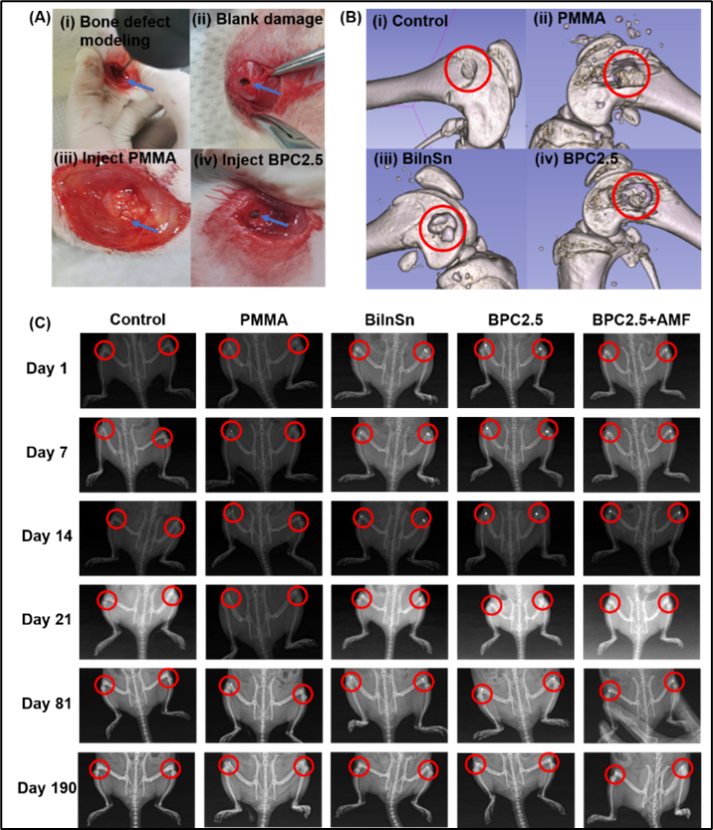

图3 铋基复合材料实现在体骨修复

针对以上挑战,联合团队结合铋基低熔点金属和临床PMMA骨水泥,创新性地设计出兼具液态-固态相变特性的可注射合金复合骨修复材料。该材料通过微创注射实现骨缺损精准填充,抗压强度较铋合金提升2.5倍。PMMA的引入使得铋合金在保持流动性的同时有效降低骨水泥的聚合放热,复合材料的最高凝固温度不超过45 ℃,显著降低热损伤风险。金属的添加使复合材料在交变磁场下表现出明显的磁热效应,体外实验证实复合材料在交变磁场下可产生可控的磁热效应——43 ℃高温杀伤骨肿瘤细胞;41 ℃温和磁热促进成骨分化。在体骨肿瘤治疗实验表明复合材料可高效消融骨肉瘤并抑制肿瘤生长。同时超过6个月的X光成像观察,植入的复合材料未发生明显移位,表明铋基复合材料与骨组织的结合具有长期稳定性,能够有效填充缺损骨,并实现持久的修复效果。更进一步地,在交变磁场下对缺损骨进行处理,组织学染色结果显示温和的磁热作用可促进骨组织再生。最后通过材料的离子释放浓度检测、细胞毒性分析、以及大鼠的肝肾功能评估,证明了本研究所设计的铋基复合材料具有良好的生物安全性。总结之,可注射铋基复合材料通过协同增强的机械强度与磁热效应,创新地实现了微创原位骨修复、骨肉瘤抑制与骨再生精准调控,为未来复杂骨修复治疗提供全新策略。